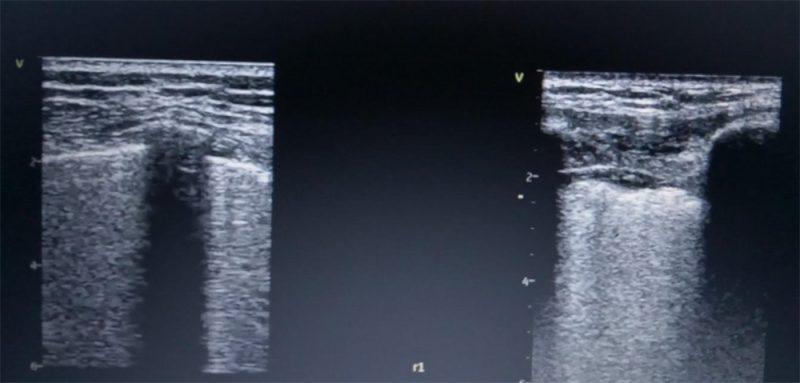

-Примената на ехото на бели дробови е голема со предност немање на радијација за разлика од КТ и рентгенграфијата. При различни дифузни заболувања како саркоидоза, реуматоиден артритис, СЛЕ, амилоидоза често се засегнати и белите дробови пришто ехографски се прикажуваат патолошки “Б“ линии.

Хиперехогените вертикални кои при белодробна конгестија се подвижни и почнуваат од глатка подвижна плеврална линија за разлика од дифузните белодробни заболувања кај кои има задебелување и ирегуларност на плевралната линија со хиперехогени вертикални линии и нивна слаба подвижност.

Ехото на бели дробови се применува и во случаи на белодробна бронхопнеумонија, ателектази, плеврални изливи и пнеумоторакс.